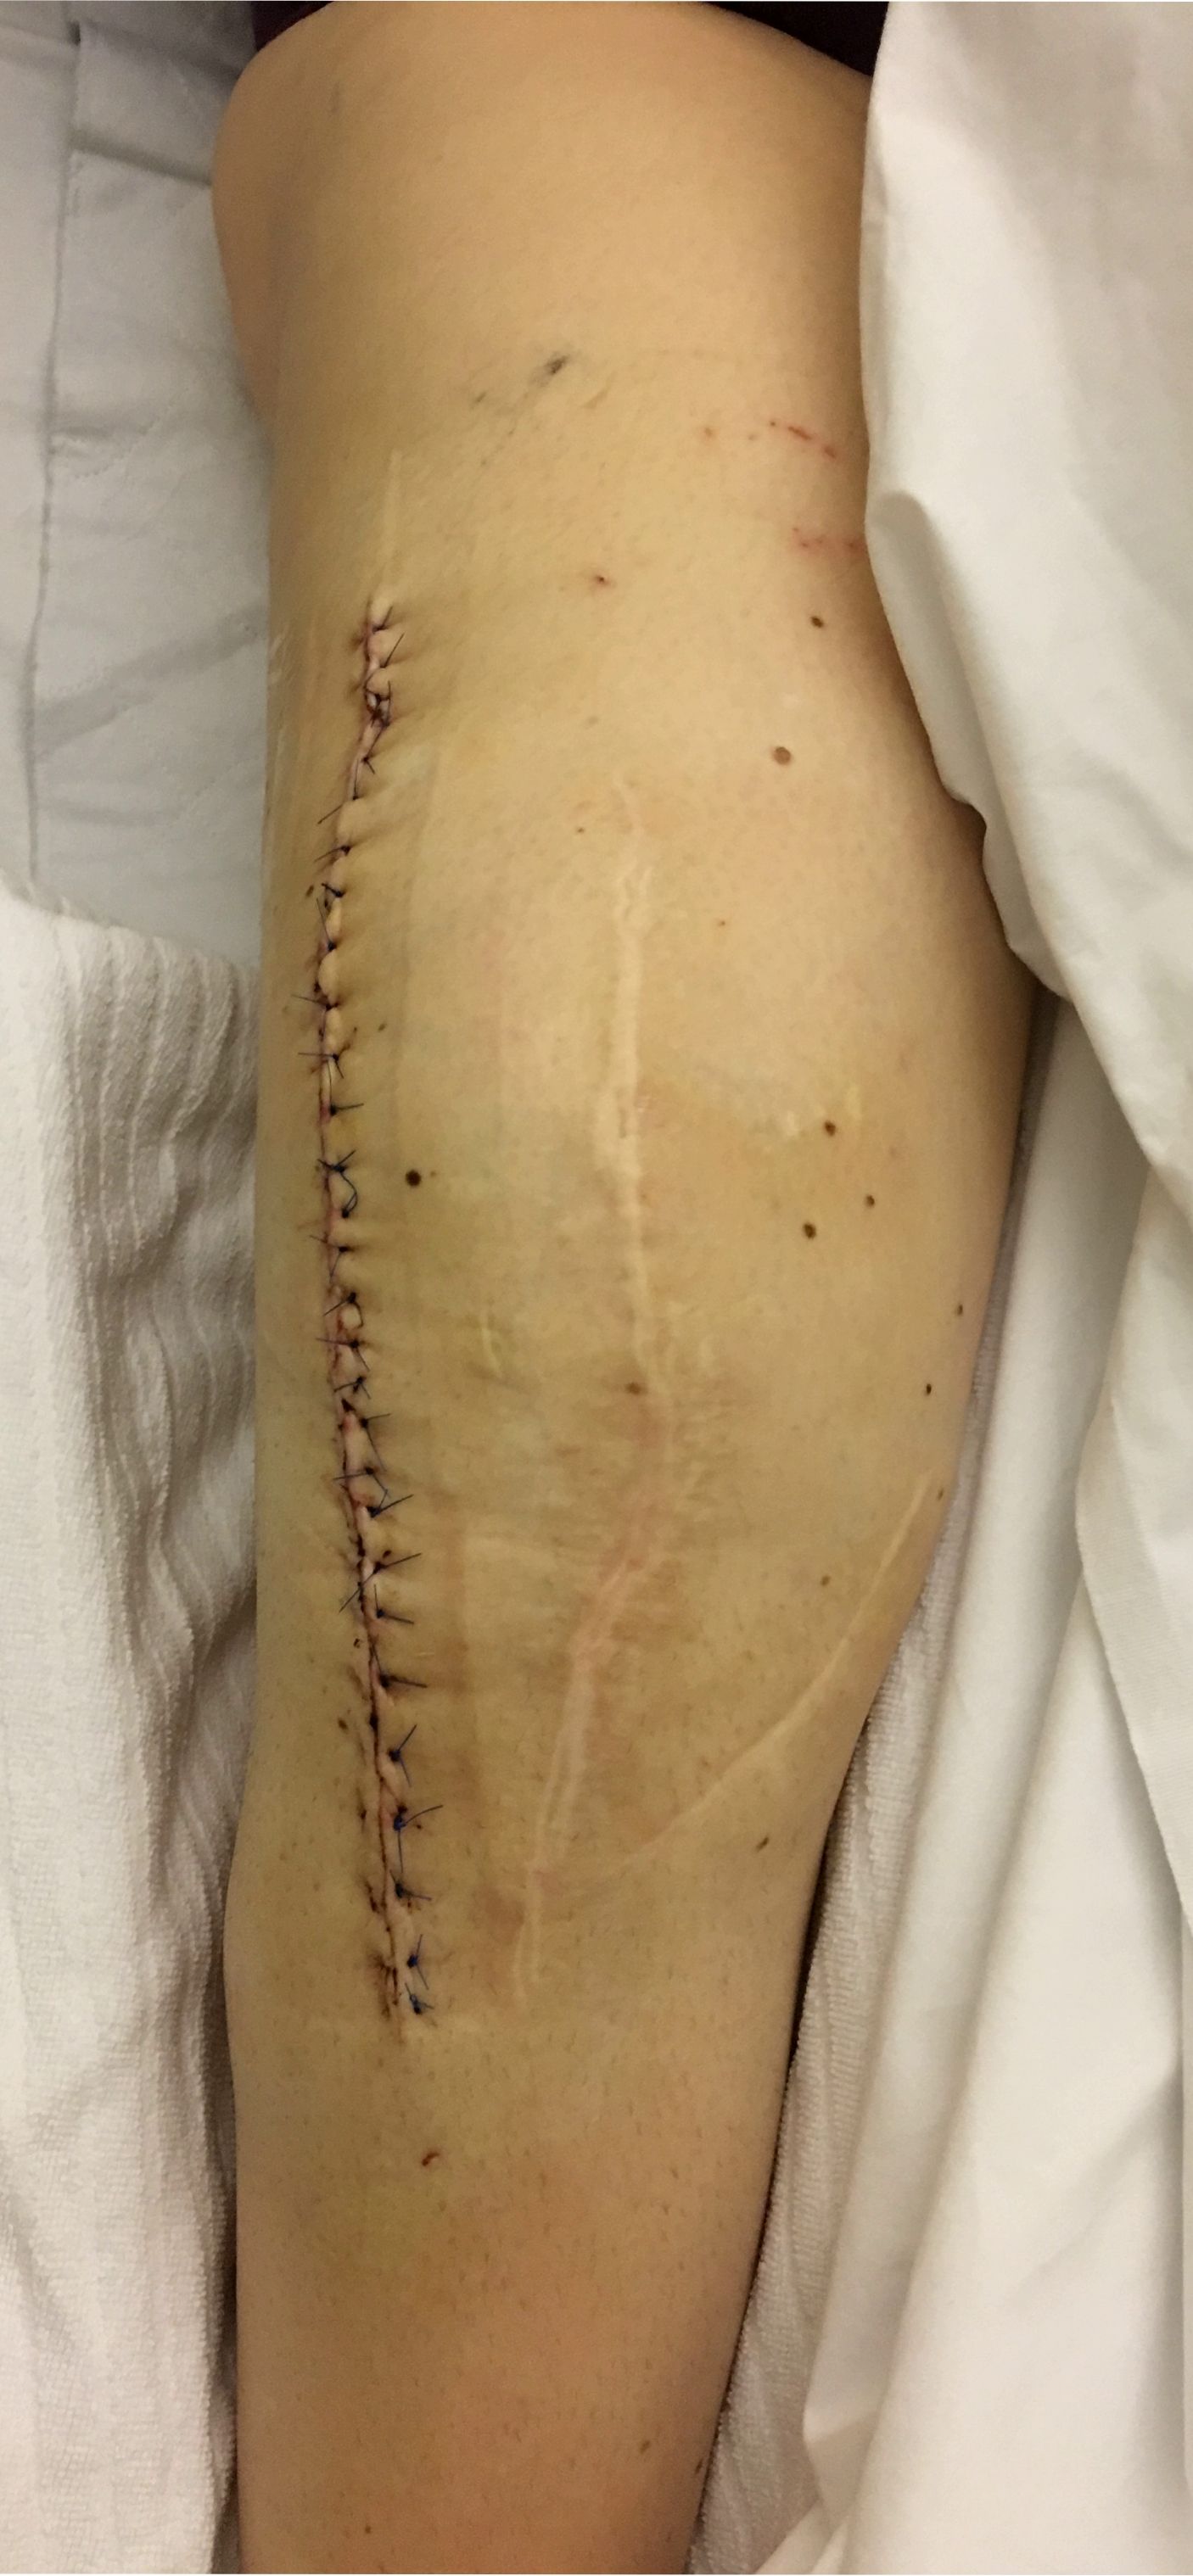

The surgical treatment depends on the causes identified using the diagnostic algorithm. There is no revision surgery for unclear pain. Only when the puzzle forms a nice picture and the diagnostic findings perfectly match with the patient’s symptoms, a revision surgery should be considered (Fig 5, 6).

For fixation and compensation of bone loss several different concepts exist. One has to understand the concept of zonal fixation (12). Based on this the revised TKA needs to be well fixed in at least two of the three fixation zones (joint, metaphyseal, diaphyseal). The fixation generally can be cemented and/or uncemented. For fixation in the metaphyseal zone sleeves and cones can be used. For fixation in the diaphyseal region either uncemented press-fit stems or cemented stems can be used. All these systems should be available in places in which revision TKA is performed. In summary, the diagnostics and treatment of an unhappy knee after TKA is a specialized one and requires a profound understanding and technical skill-set of a specialized knee revision surgeon (Fig 8). Only when the cause(s) of the problem are identified, revision surgery should be performed.